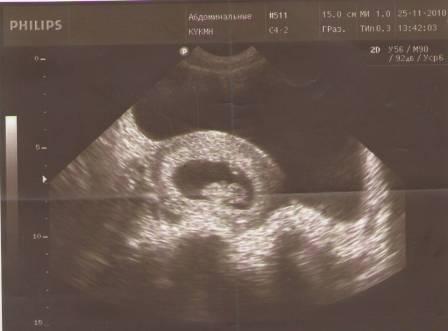

Всем привет. вчера мы сходили на УЗИ, вот что у нас получилось:

Узистка сказала, что срок 10 полных недель. все у нас в норме. тонуса нет, воды в норме, и там какой-то КТР 2,5, или 2,8. Что такое КТР ???? объясните плиз кто знает, а то не поняла я.